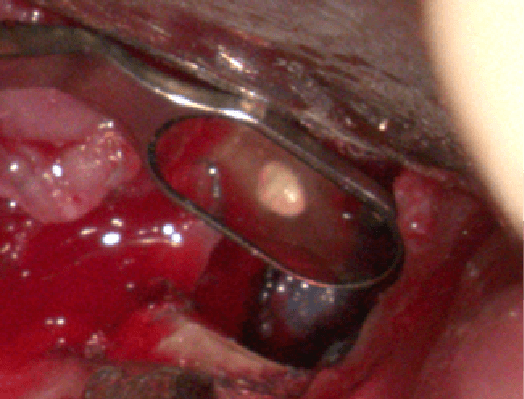

左圖紅線中為之前醫師不小心斷裂的器械,中間的照片可以看到白白的那節已經消失,右圖為完成根管治療以及假牙製作